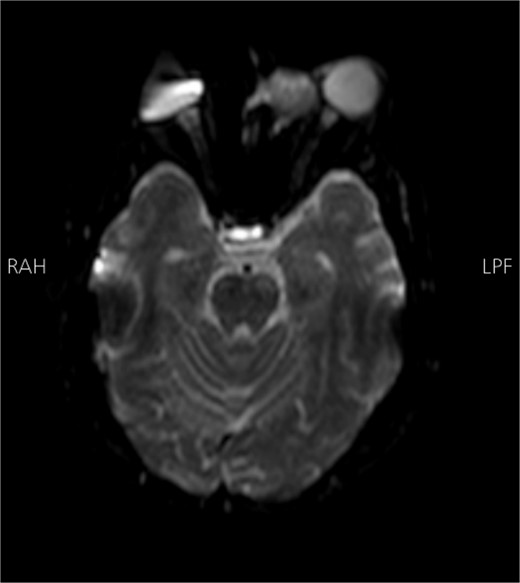

Radiological findings from a high-resolution CT scan (Fig. 1) revealed bilateral basal ganglia hypodense areas suggestive of chronic ischemia and a more lateral hypodense area toward the left basal ganglia indicative of subacute ischemia. A coronal cut showed an iso-dense expansible soft tissue lesion with internal foci of calcifications centered in the anterior aspect of the left ethmoid sinus with protrusion to the left orbital conus, pushing the medial rectus muscle laterally with complete obliteration of the left frontal sinus. Brain MRI with FLAIR (Fig. 2) showed an abnormal hyperintense signal in the left cavernous sinus and a left ethmoidal sinus synovial tumor.

Brain MRI DWI sequence showing abnormal hyper-intense signal (bright) in the distribution of the left cavernous sinus. The left ethmoidal sinus synovial tumor is also noted.